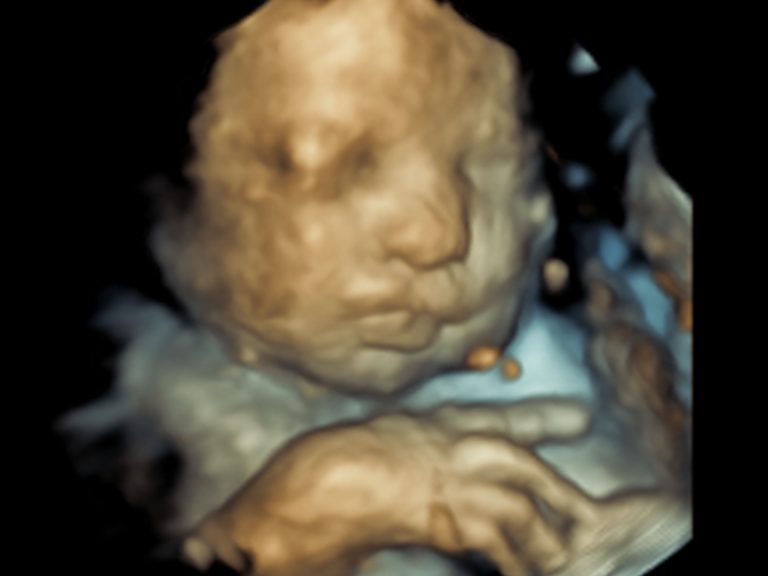

3D ultrasound scan of baby, closeup Stock Photo Alamy Are 3D Baby Scans Worth It As a general rule, qualified sonographers aim to use as little energy as possible when performing a scan to keep keep exposure to baby to a minimum. 3d ultrasounds can be worth it if your doctor wants to monitor your baby more closely. Learn when to get a 3d ultrasound and what to expect depending on your pregnancy stage. And. Are 3D Baby Scans Worth It.

Ultrasound Baby Face On X 3D 4D ultrasound scan This Are 3D Baby Scans Worth It 3d ultrasounds can be worth it if your doctor wants to monitor your baby more closely. Find out how doctors use ultrasound to assess your baby's health and development. Medical conditions such as cleft lips may be able to be better diagnosed in 3d. But before you do, it’s important to understand what 3d sonograms and 4d ultrasounds are, when. Are 3D Baby Scans Worth It.